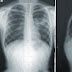

Lung Cancer - Types Of Cancer, Staging & Grading, Treatment Of Lung Cancer